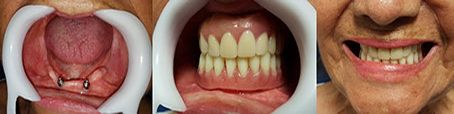

• Prótesis

El objetivo es devolver la estética y función que se pierden ante la ausencia de piezas dentarias. Para lograrlo según cada caso en particular se realizan prótesis fijas o como alternativa prótesis removibles. Vemos un tratamiento de prótesis completa inferior con colocación de 2 implantes en la zona de caninos para utilización de ball attach, mejorando notablemente la retención de la prótesis inferior.